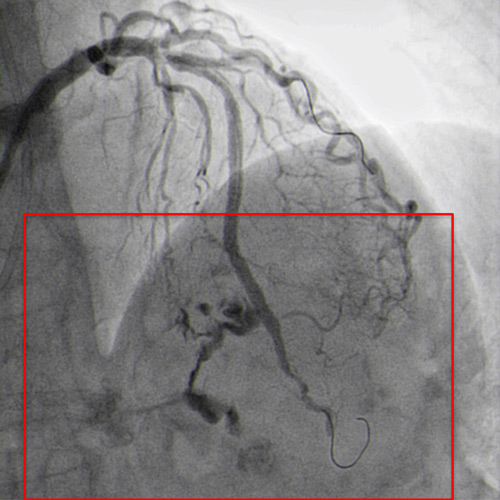

JR 4.0 guiding catheter exchanged with JL 4.0 to achieve left main (ping-pong) and position a parallel wire in left anterior descending (Figure 7.2). In the first wire we have the balloon, in the second wire a covered stent, but the perforation resolved only with balloon dilatation so we avoided, at this time to implant a covered stent.

JR 4.0 guiding catheter exchanged with JL 4.0 to achieve left main ping-pong (Figure 7.2).

After several minutes no contrast protrusion, the perforation appeared resolved, so the second wire in the JL catheter was removed and PCI completed with another DES implantation in proximal LAD (Figure 8.1).

Additional DES implanted to proximal LAD (Figure 8.1)

The angiographic control showed mild perforation recurrence (Figure 8.2).

Perforation still present (Figure 8.2)

Implantation of the covered stent (Figure 9).

Covered stent implanted (Figure 9)